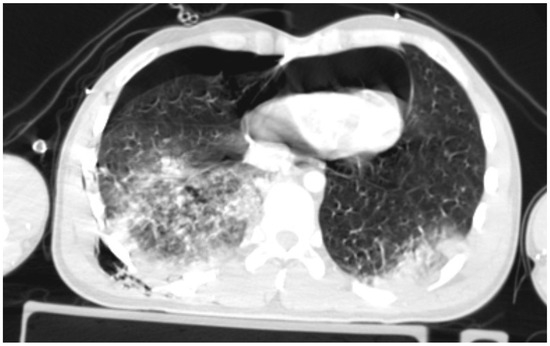

A patient with blunt trauma may have several severe injuries; each of them, if untreated, can be fatal. A post-mortem examination of patients after falls from heights did not reveal the presence of isolated pneumopericardium; it was always accompanied by other severe injuries [5]. The clinical picture of increasing pneumopericardium may be confused by concurrent conditions: cardiac contusion, pneumothorax, hemorrhage, or spinal shock [20]. Initially, our patient presented symptoms that could suggest both tension pneumothorax and tension pneumopericardium. Bedside ultrasonography revealed two significant symptoms: the absence of pleural sliding on the right side of the chest and the lack of heart image in the available ultrasound imaging windows. Cheryl L. Reid et al. [21] in 1983 described the characteristic signs of pneumomediastinum and pneumopericardium as an “air gap sign”. This symptom involves the cyclic appearance of air echoes, thus covering the image of the heart during systole and early phase of diastole of ventricles. It is caused by a physical shift and a reduction in the volume of air due to changes in the volume of the ventricles during the heartbeat [21,22], but this symptom does not occur in cases of tension pneumopericardium because elevated pressure in the pericardium keeps the heart under the layer of air. Due to the more frequent occurrence of tension pneumothorax compared to tension pneumopericardium, drainage of the right pleural cavity was performed, achieving the initial improvement in the patient’s condition, which allowed for performing CT scanning in the polytrauma protocol, where symptoms of tension pneumopericardium were seen. Heimer et al. [5] stated “ballooning” as a typical sign of tension pneumopericardium in CT scanning, which involves the protrusion of the pericardium beyond the line drawn of the apex of the heart and perpendicular to its axis, as shown in Figure 4. If the pericardium does not pass beyond this line, the pneumopericardium is considered normotensive.

Figure 4. Ballooning is a sign of tension pneumopericardium.